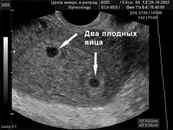

Диагностика на ранних сроках: Современные методы ультразвукового исследования позволяют выявить многоплодную беременность уже на ранних сроках — обычно на 6-8 неделе. При этом врачи могут не только подтвердить наличие нескольких эмбрионов, но и оценить их развитие и состояние.

Выявить такую беременность помогают размеры матки, которая не соответствует по сроку одноплодной, быстрое увеличение ее на следующих приемах. Очень важно отличить ее от пузырного заноса. Для этого необходимо проводить дополнительные исследования с десятой недели: электрокардиография (позволит выявить сердечные комплексы при нескольких эмбрионах); фото УЗИ может показать количество детей, но не всегда бывает точным изображение (возможно отмирание плода или выход одного, который прятался ранее). Поэтому следует выполнять такое исследование по неделям, чтобы контролировать развитие всех плодов. После тридцатой недели необходимо выполнять допплерографию и кардиотокографию. Если будут выявлены любые отклонения, необходима срочная госпитализация.

Диагностика многоплодной беременности обычно осуществляется с помощью ультразвукового исследования (УЗИ), которое позволяет визуализировать количество плодов. Обычно первое УЗИ проводится на сроке 6-8 недель, и в большинстве случаев уже на этом этапе можно определить, сколько эмбрионов развивается в матке.